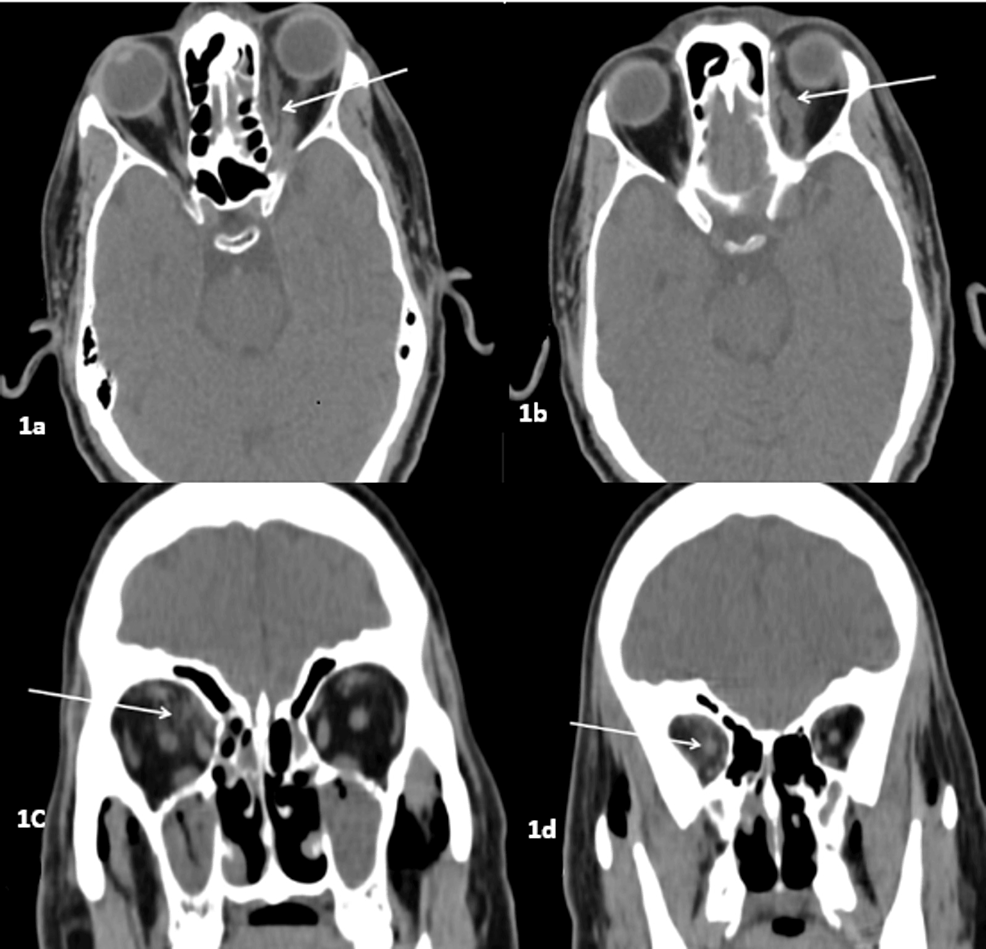

The Radiological Spectrum of Rhino-Oculo-Cerebral Mucormycosis

ROCM is a life-threatening invasive fungal infection, especially in an immunocompromised state. ROCM is characterized by a variety of imaging abnormalities on CT and MRI, although nonspecific. Imaging aids in suspicion or early diagnosis in appropriate clinical contexts, particularly in an immunocompromised state, and in determining the...